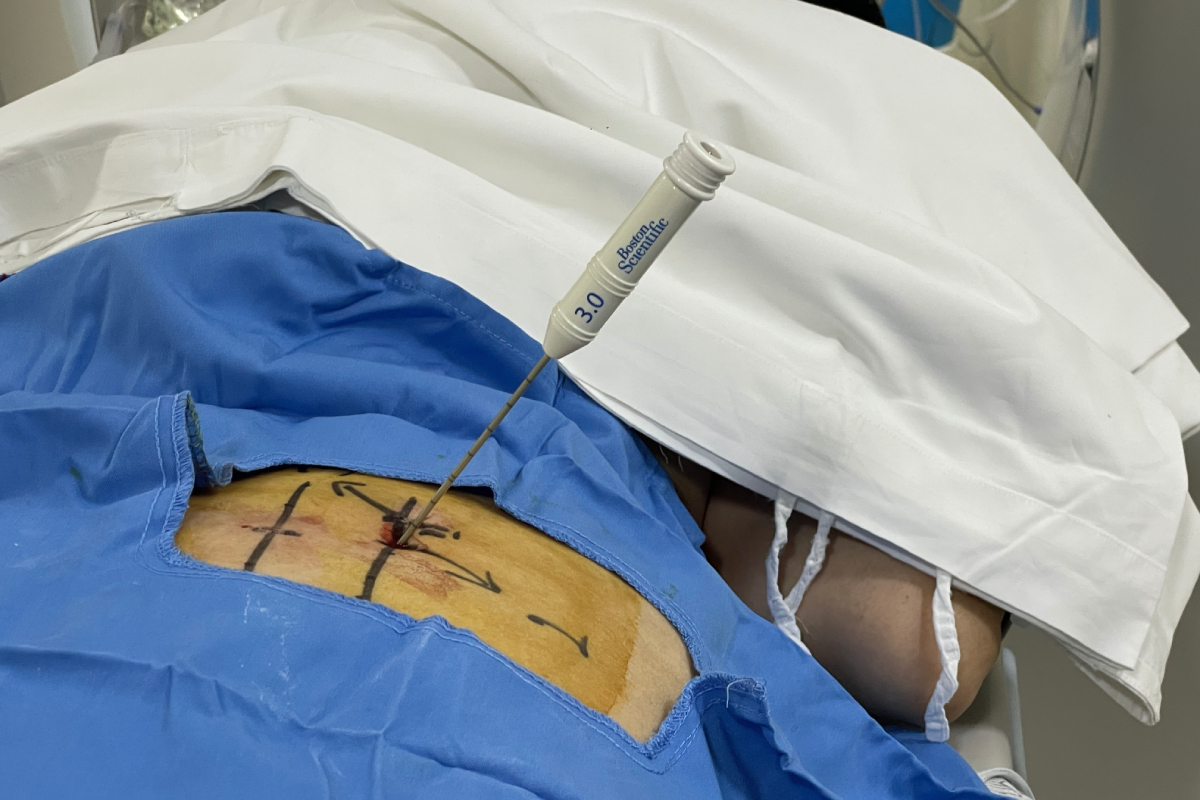

Home Photos Bone tumor radiofrequency ablation Blog Bone tumor radiofrequency ablation Radiofrequency ablation of hepatic metastatic disease using advanced interventional radiology techniques. Percutaneous radiofrequency ablation of a metastatic lesion in the scapular region under ultrasound guidance. Excisional biopsy of a lymph node at the Interventional Radiology Service. For the first time in Armenia, a transjugular intrahepatic portosystemic shunt (TIPS) has been performed. Thyroid nodule ablation Embolization of an intraductal tumor Intrahepatic Tumor Biopsy